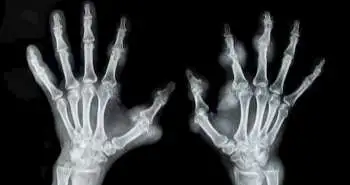

To assess whether the drop in BMD of the hands (BMD loss), as defined by DXR 3 months after diagnosis, anticipate radiographic joint damage following one and two years within patients with early RA.

Digital X-ray radiogrammetry (DXR) is computerised analysis technique to estimate peripheral bone mineral density (BMD). Literuture reports that previous DXR-BMD studies have been based on 12-month change, and by that time, conventional X-ray assessments of joint damage are at least as informative about disease progression. This study reports the DXR-BMD loss during the initial 3 months independently predicted radiographic joint damage at 1 year in patients with early RA.

A total of 167 of these individuals with RA were incorporated in the analysis. Medicine was prescribed under Swedish guidelines, and then a follow up of 2 years was done. Antibodies and rheumatoid factor to cyclic citrullinated peptides were estimated at baseline, and 28-joint Disease Activity Score (DAS28) was evaluated at every visit. Feet and hands radiographs were taken at baseline, three months (hands only), one and two years. The Larsen score assessed baseline and 1-year and 2-year radiographs. Radiographic progression was determined as a difference in Larsen score over the least detectable change. DXR-BMD was estimated at baseline and following three months. The 0.25 and 2.5 mg/cm2/month decline in BMD exhibited a moderate BMD loss and declined up to 2.5 mg/cm2/month described as a severe BMD loss. Multivariate regression was implemented to test the relationship within DXR-BMD loss and radiographic destruction, involving adjustments for possible confounders.

In total, 15% of patients showed severe, and 44% showed moderate DXR-BMD loss at the initial three months. Out of these patients, 19% exhibited radiographic progression at one year and 35% at two years. During multiple regression analyses, a significant relationship was seen between DXR-BMD loss and increase in Larsen score between baseline and one year.

DXR-BMD loss at the first three months autonomously estimated the radiographic joint destruction at one year among individuals with early RA. Thus, DXR-BMD may be a beneficial tool to identify ongoing joint damage and thereby to enhance individualisation of treatment during early RA.